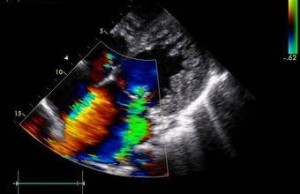

结合心脏彩色多普勒超声和心电图检查,诊断为心肌致密化不全、心功能三级、B型预激综合征,以及频发室性期前收缩二联律和呼吸功能不全,